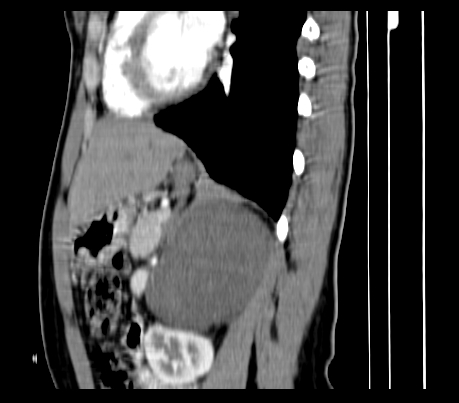

标题: CT23915:女 20岁 全身长疙瘩三年 今日多体位查 看看吧 [打印本页]

标题: CT23915:女 20岁 全身长疙瘩三年 今日多体位查 看看吧

胸部

神经纤维瘤病

支持神经纤维瘤。

支持 神经纤维瘤病。